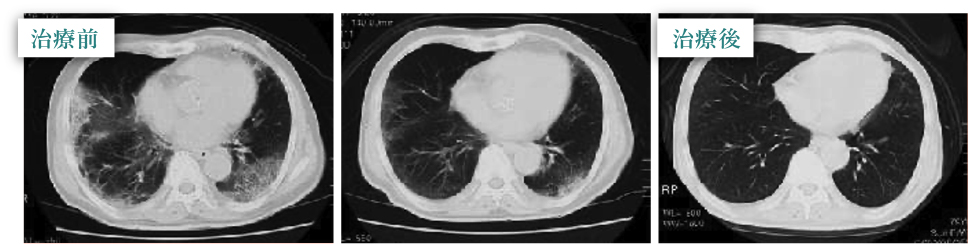

治療実例 70歳 男性 Cさん

潜在性肺血栓症状の疑いがあり他院に肺炎として入院。2ヶ月間の治療後、 一番左側の胸部 CT では後部と右中肺葉に未だ陰部が残り、 80メートルほど歩くだけで

呼吸困難に陥り、動怪が激しくなる状態。

金滞点滴療法を施術すると真ん中に示すように陰影は大方消失し、更に右の写真についてはほぼ殆消失し、

呼吸困難の症状も改善した。往復2キロを歩いても呼吸困難にもならず、激しい動怪も起こらなくなった。